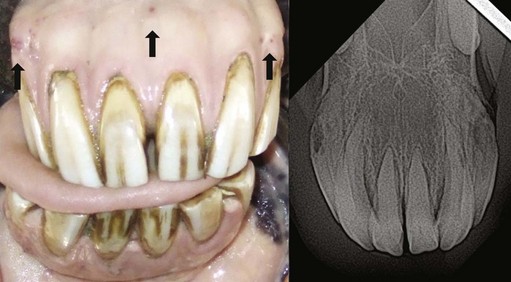

More recently, a more severe form of incisor periodontal disease has been recognized in geriatric equids that is associated with cemental hyoplasia, and hyperplasia and radiographic lytic changes.2427 The exact etiopathogenesis of this disease has not been determined, but pathological studies show it to be an odontoclastic resorption of affected incisors (also of canine teeth) with subsequent marked deposition of cement on these teeth, termed equine odontoclastic tooth resorption and hypercementosis (EOTRH; discussed in Ch. 10). Affected animals may present with clinical signs associated with pain, such as masticatory and bitting problems, and halitosis (Fig. 18.8). Initially, this condition presents as mild gingival inflammation and edema with small lytic changes in the mid reserve crown incisor on radiographic examination.25 With progression of the condition, draining tracts may develop in the gingiva, and this may be accompanied by gingival recession, or marked subgingival swelling of incisors, reflecting hypercementosis of their reserve crown and apex. Radiographically, progression of the disease is characterized by lysis of the incisors in an apical direction and an increase in the thickness of the lytic areas to involve the dentin. Loss of interdental bone and widening of the periodontal ligament may also be observed on radiographs. Clinically advanced cases may have painful mobile incisors. Hypercementosis (subgingival nodular enlargements) of portions or all of the subgingival incisors may also be observed on radiographs in some advanced cases (Fig. 18.9).

image

Fig. 18.8 Enlargement of thickness of reserve crown of 203 and 303 (identical to 103 and 403) due to hypercementosis associated with equine odontoclastic tooth resorption and hypercementosis. The horse was asymptomatic, and the disease was identified on oral examination. All the incisors were stable and non-painful to manipulation, but firm palpation of 303 and 403 reserve crowns was painful.

Fig. 18.9 This 20-year-old Thoroughbred was reported to refuse to bite carrots for over one year. Enlargement of all incisor reserve crowns is prominent with gingival recession, and draining tracts visible (at arrows). Radiographs showed extensive lysis and hypercementosis of 103 and 203, typical of equine odontoclastic tooth resorption and hypercementosis, with radiographic changes in all the other incisors.